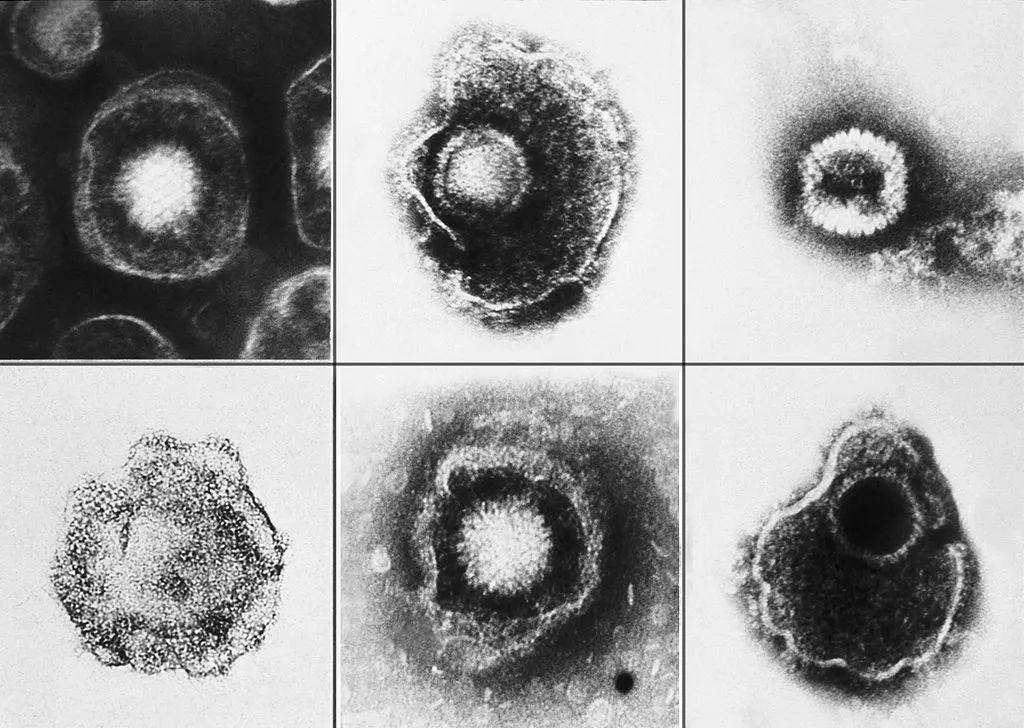

它们都是由同一种水痘-带状疱疹病毒(varicella zoster virus,简称VZV)引起的感染。而这种病毒广泛分布在全世界,人类是它唯一的宿主。

电子显微镜的水痘带状疱疹病毒约放大倍数为150,000倍

人类疱疹病毒

注:在医学上,人类的疱疹病毒一共有8型,分别是单纯疱疹病毒1型、单纯疱疹病毒2型、水痘-带状疱疹病毒、EB病毒、巨细胞病毒、人类疱疹病毒6型、人类疱疹病毒7型、人类疱疹病毒8型